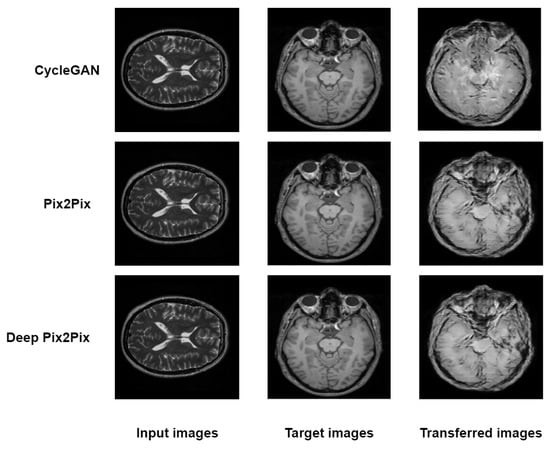

The three models, including cyclegan, pix2pix and proposed deep pix2pix, try to generate synthetic images from one view to another view for qualitative analysis. As shown in Figure 3, the proposed deep pix2pix model shows the most accurate result compared to the rest of the models used in the experiment, while the cyclegan model performs the worst qualitative analysis.

Figure 3.

Testing images of CycleGan, Pix2Pix and Deep Pix2Pix.